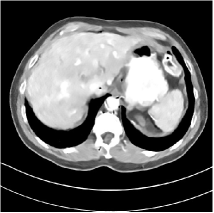

Fig. 3: Three examples (from top to bottom) of the reconstructed testing images using Momentum-Net with SimpleCNN (the second column), with SimpleCNN-RSN (the third column), and with Dn-RSN (the fourth column). The compared WavResNet denoised images are shown in the first column, and the reference images are in the fifth column. See their FBP images in Fig. 4.

Refer to caption

Fig. 4: FBP images of test examples.

3.2 Proposed Momentum-Net with SimpleCNN

Fig. 2 shows that the proposed Momentum-Net with SimpleCNN decreases RMSE dramatically in the first 30 layers, and tends to converge in 50 layers. The Momentum-Net reduces the mean RMSE value by 4.5 HU and gives smaller standard deviations in RMSE, compared to WavResNet, as reported in Table 1. This implies that the proposed Momentum-Net with SimpleCNN can improve both the accuracy and stability of low-dose CT image reconstruction than a state-of-the-art image denoising deep NN, WavResNet. The proposed Momentum-Net with SimpleCNN better removes noise and streak artifacts than WavResNet. It also provides clearer reconstructions of some details; see, in Fig. 3, the boundaries shown in the zoomed region at the top-right corner in the first example, the arrow pointed structures in zoomed areas of the second example, and the arrow pointed tissues in the left zoomed region in the third example.

3.3 Momentum-Nets involving RSN-based training

We show the reconstructed examples by Momentum-Net with SimpleCNN-RSN and Dn-RSN in the third and fourth columns of Fig. 3 respectively. Comparing the first three and the last columns in Fig. 3, we observe that Momentum-Net with SimpleCNN-RSN provides generally noisier reconstructions than WavResNet and Momentum-Net with SimpleCNN. However, Momentum-Net with SimpleCNN-RSN sometimes can provide clearer details than WavResNet. For example, in the right zoomed box of the second example, Momentum-Net with SimpleCNN-RSN shows better reconstruction quality for the arrow pointed structures than WavResNet, and in the left zoomed box in the third row, the former gives clearer small tissues marked by red arrows than the latter. Table 1 reports that Momentum-Net with SimpleCNN-RSN is approximately 2.9 RMSE (HU) higher than WavResNet, while it has smaller standard deviations. This implies that Momentum-Net with SimpleCNN-RSN is more stable than WavResNet, although it may not provide better image qualities. Momentum-Net with Dn-RSN, however, provides the worst visual and numerical results among the compared four methods in this paper.